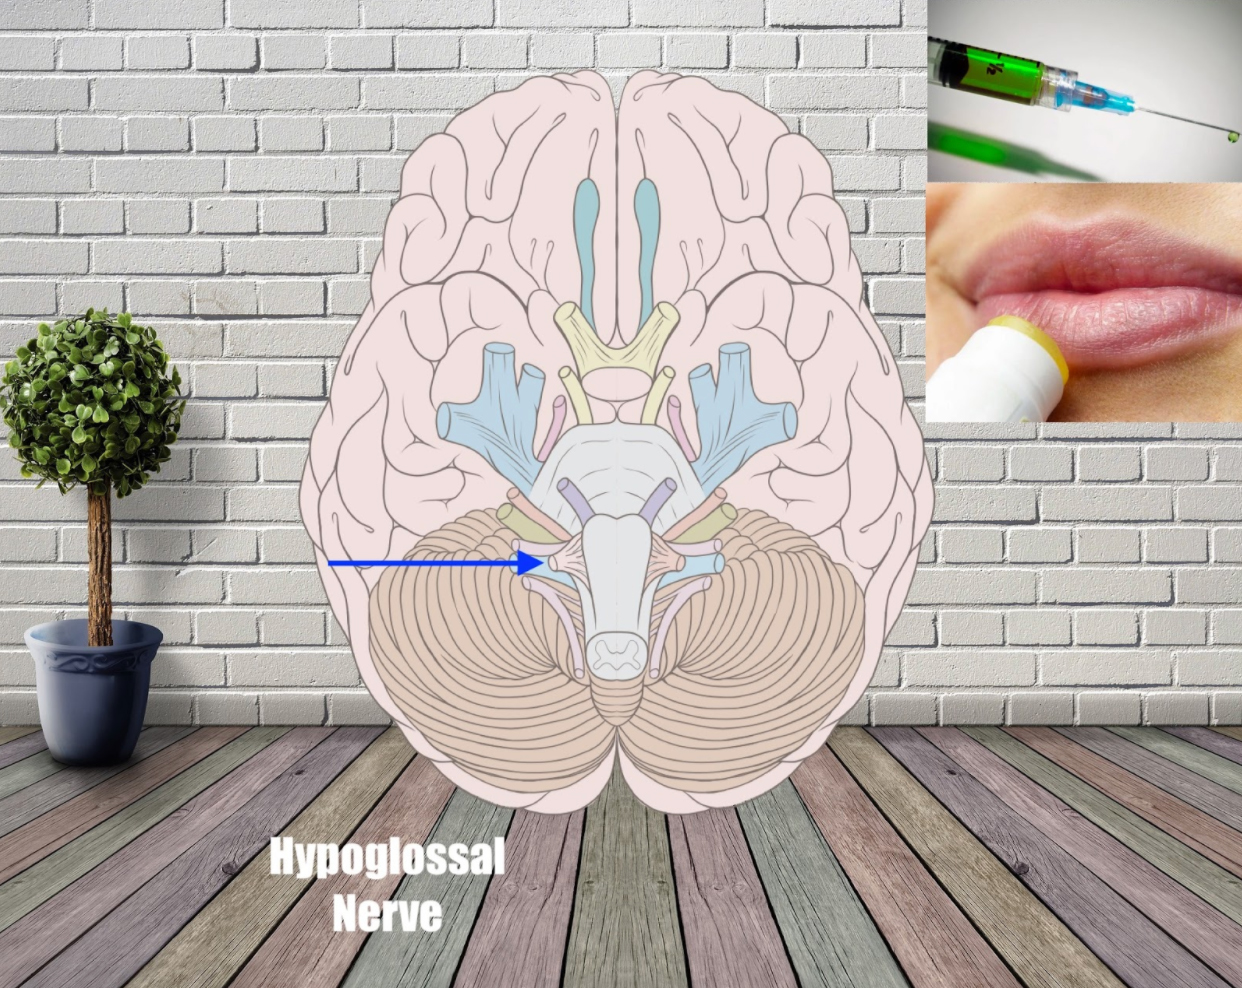

Hypoglossal nerve (Motor) – ‘Lip Gloss, Hypodermic Needle’

Lip gloss is back! This time with a hypodermic needle injecting a nerve agent into it.

It’s a weird image, right?

Yes, and that’s what makes it easy to remember this term.

Again, to remember that it’s a motor nerve, you can add a motor to the image. It could be a motor that is helping the hypodermic needle operate, for example.